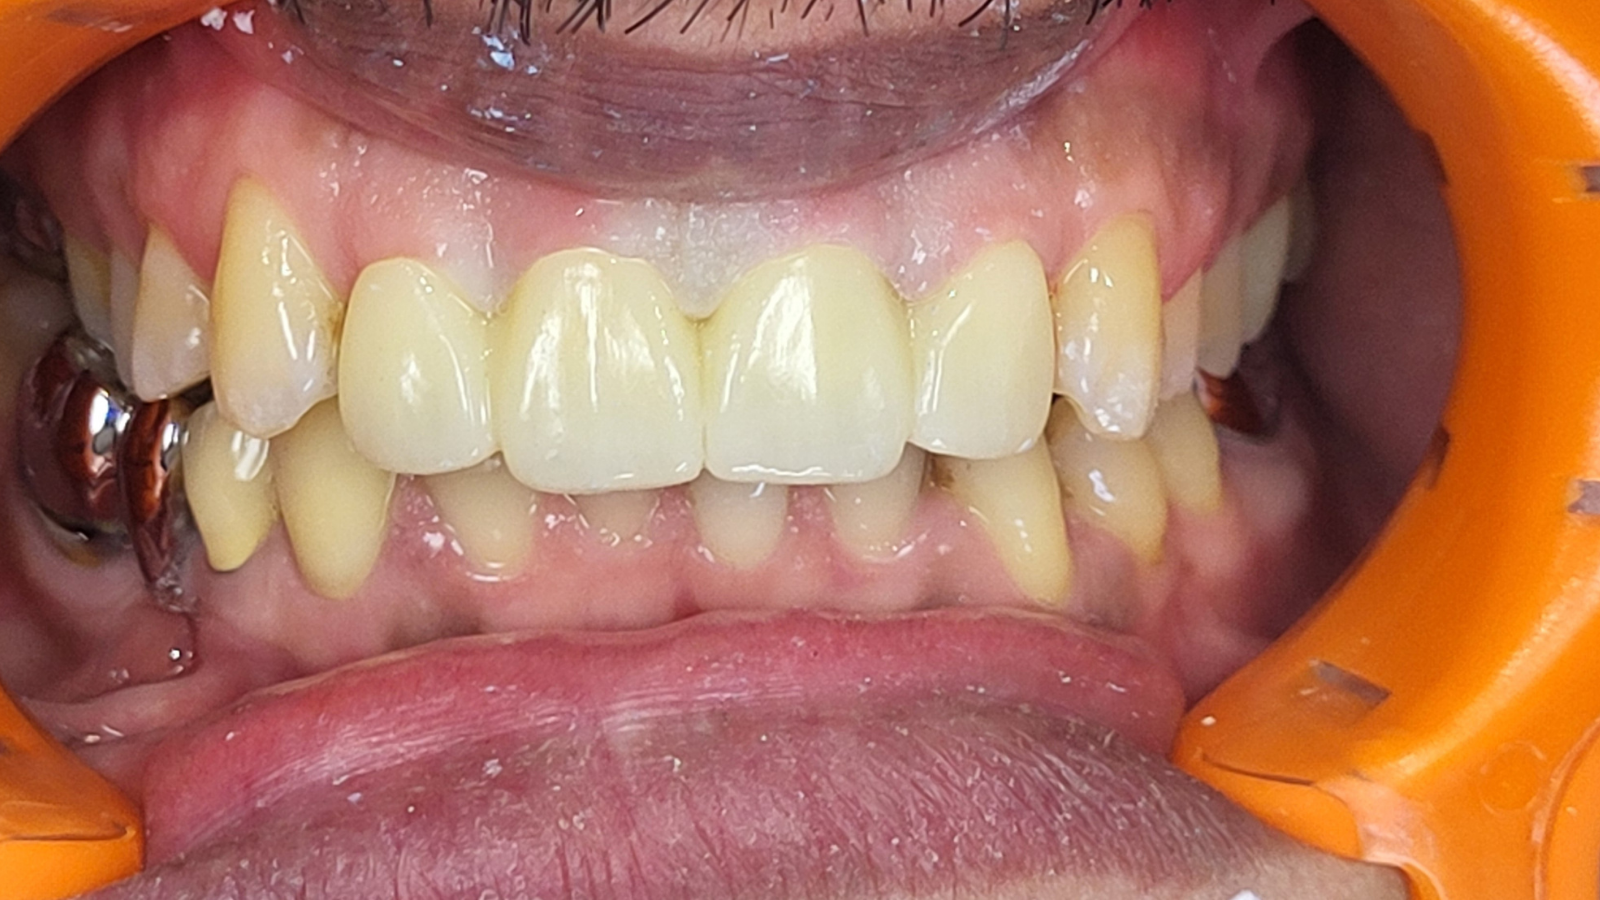

Réhabilitation complète avec mise en charge immédiate (4 implants bas / 6 implants haut)

Le patient se présente avec des dents qui bougent, en haut et en bas.

Nous avons commencé par la mâchoire inférieure avec 4 implants et une mise en charge immédiate.

Trois mois après, le haut a été fait avec le même principe avec 6 implants.

Cette fois-ci, il existait un déficit osseux, résolu par une technique d’expansion sans avoir recours à la greffe d’os.

Les prothèses réalisées sont vissées, ce qui permet de les enlever, les nettoyer une fois par an, ou résoudre n’importe quel problème.